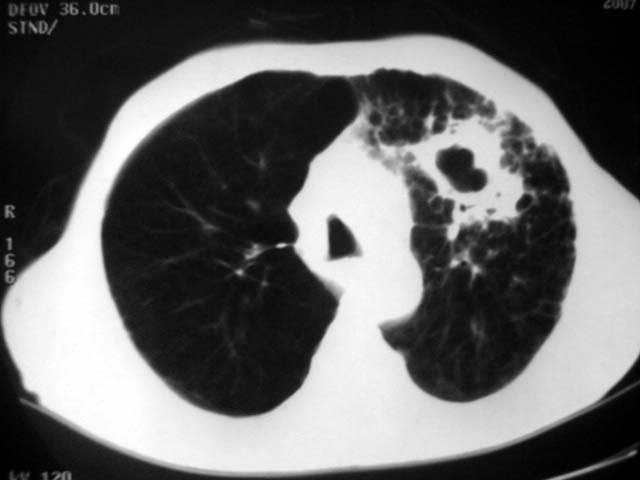

以下是引用zjzjr在2007-9-4 17:00:00的发言:[br]双上肺继发型结核伴左上肺空洞形成.慢性支气管炎伴肺气肿.

以下是引用liuzheng_9326在2007-9-4 16:23:00的发言:[br]痰检未见结核菌, 治疗后症状好转。图像符合陈旧性结核伴感染。